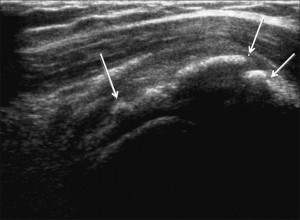

• La phase formative . Le dépôt mesure souvent moins de 1 cm. Cette phase est de durée indeterminée, et peut être associée à des douleurs. En effet, en présence d’une volumineuse calcification , cette dernière peut déformer le tendon en l’épaississant et en le « durcissant ». De cette modification de la structure tendineuse peut résulter en un conflit (une sorte de friction douloureuse) entre le tendon et l’acromion (l’os qui constitue l’épaulette). A cette phase, la calcification peut aussi être responsable d’un processus inflammatoire autour de cette dernière qui fragilise les fibres tendineuses. A ce stade la calcification a une consistance comparable à de la pate de dentifrice ou du mastic . On l’a dit pâteuse ou crayeuse (comme de la poudre agglomérée) (Fig 1). Elle peut être aussi plus dure et de type « pierreuse »(Fig 2).

(Fig1) . Calcification « molle » car peu absorbante à l’échographie.